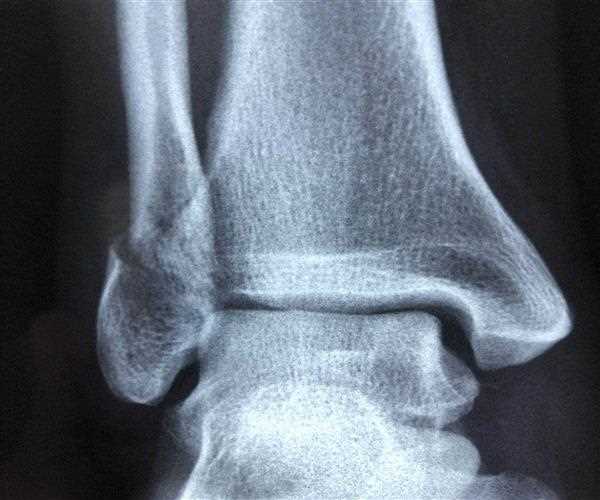

X-rays are often used to diagnose spiral fractures. Other tests used to diagnose spinal fractures include:

Without proper imaging, spiral fractures can be confused with other types of fractures such as oblique fractures.

Spiral fractures look like bottle openers and can be recognized by scanning or X-ray.